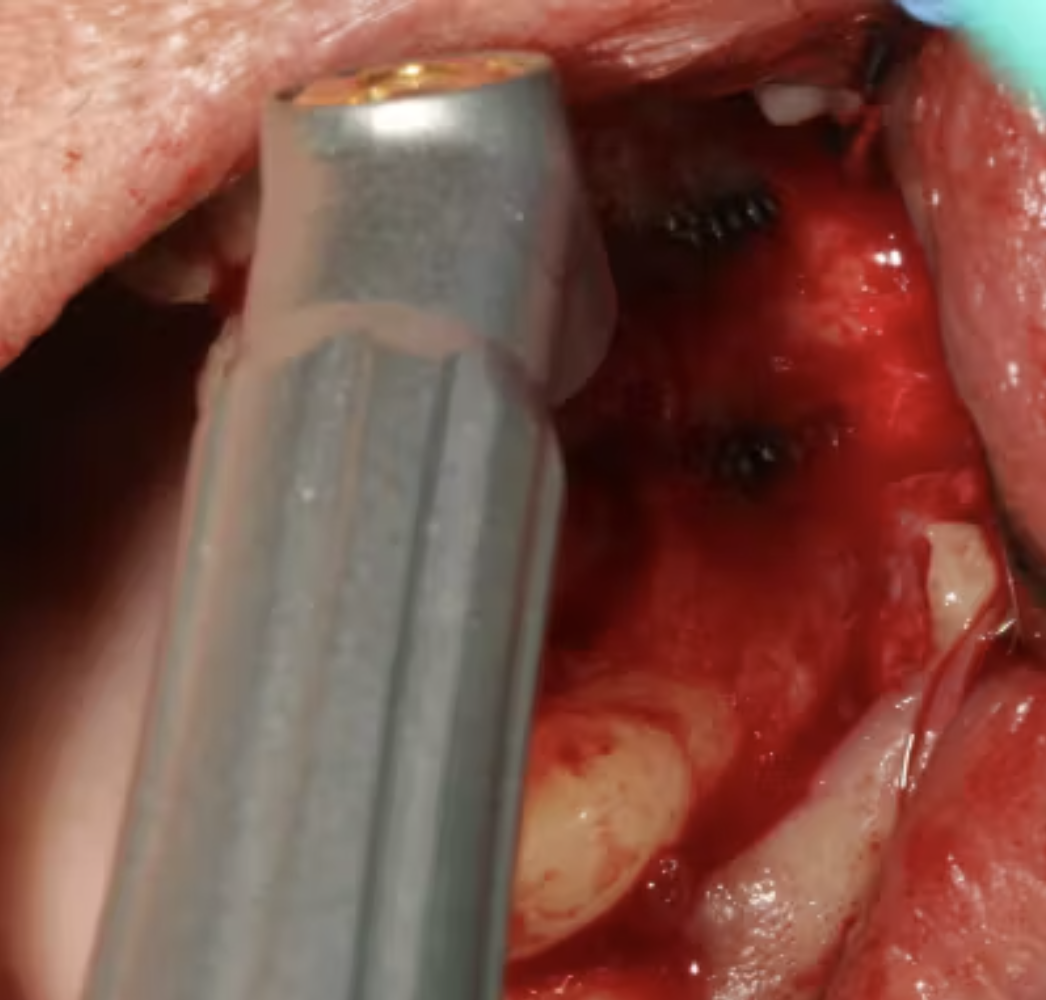

(Hình 3: Miếng bông tẩm axit citric 60% dùng để khử độc ổ implant)